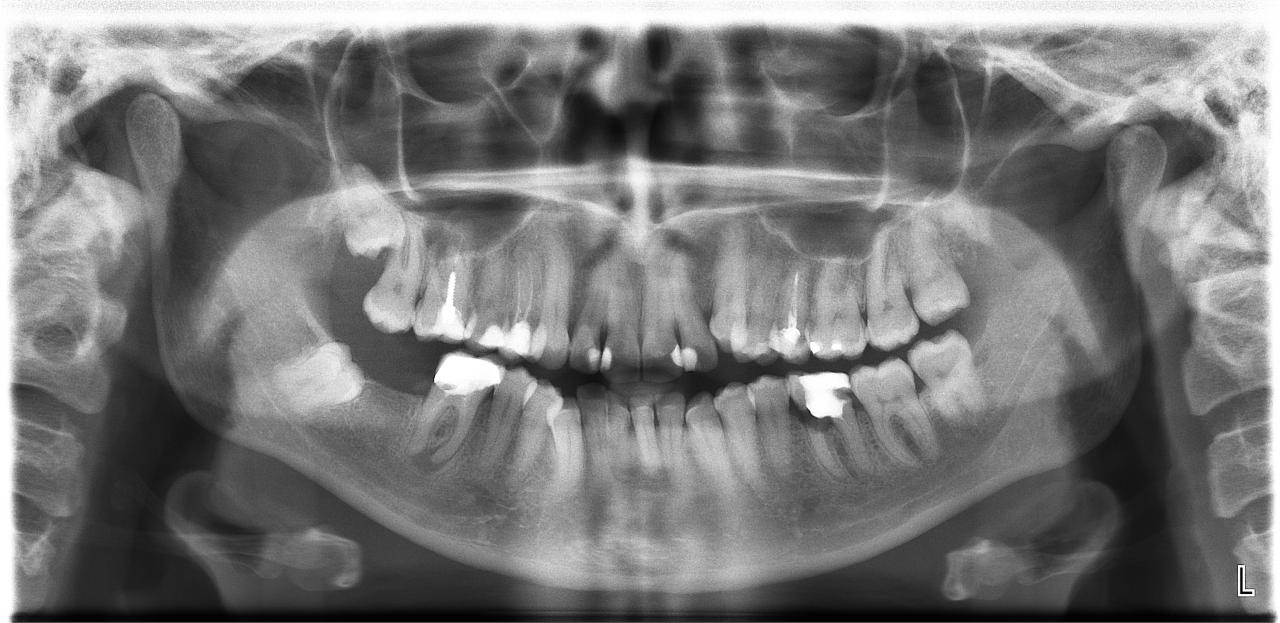

Вложение 8684927Хотела мнение коллег услышать по наличию проблем, как мне показалось( может показалось), пациент думает, что проблемы минимальные, а я запугиваю. Разрешение на вывешивание снимка получено.

все грустно...шестерки нижние удаляем... центральные резцы низ - как-то грустно тоже.... зря человек спокойно живет... пора давно бить в бубны.... жевательных мало.... (конечно бывает и хуже....но тут реально грусть-тоска)... визуально - покой - на самом деле - бомба замедленного действия...

На первый взгляд: 6 слева внизу и 8 справа вверху на удаление, за правую шестерку думаю стоит побороться, левая верхняя 5-ка- нужна повторная эндодондия, скученность, дистопия в фронтальной группе зубов- не помешала бы помощь ортодонта.

самая печаль - 16. небольшие шансы на ретрит. хирургически спасать нет - альтернатива удаление.

14 - ревизия каналов обязательна.

36 - при возможности качественного пломбирования дист корня можно предложить гемисекцию.

46 - шансы на ретрит невелики, но если возможно то наверное надо. резекция возможна.

Пациентка допускает мысль-возможность имплантации?

если да, то никаких спасательных операций.